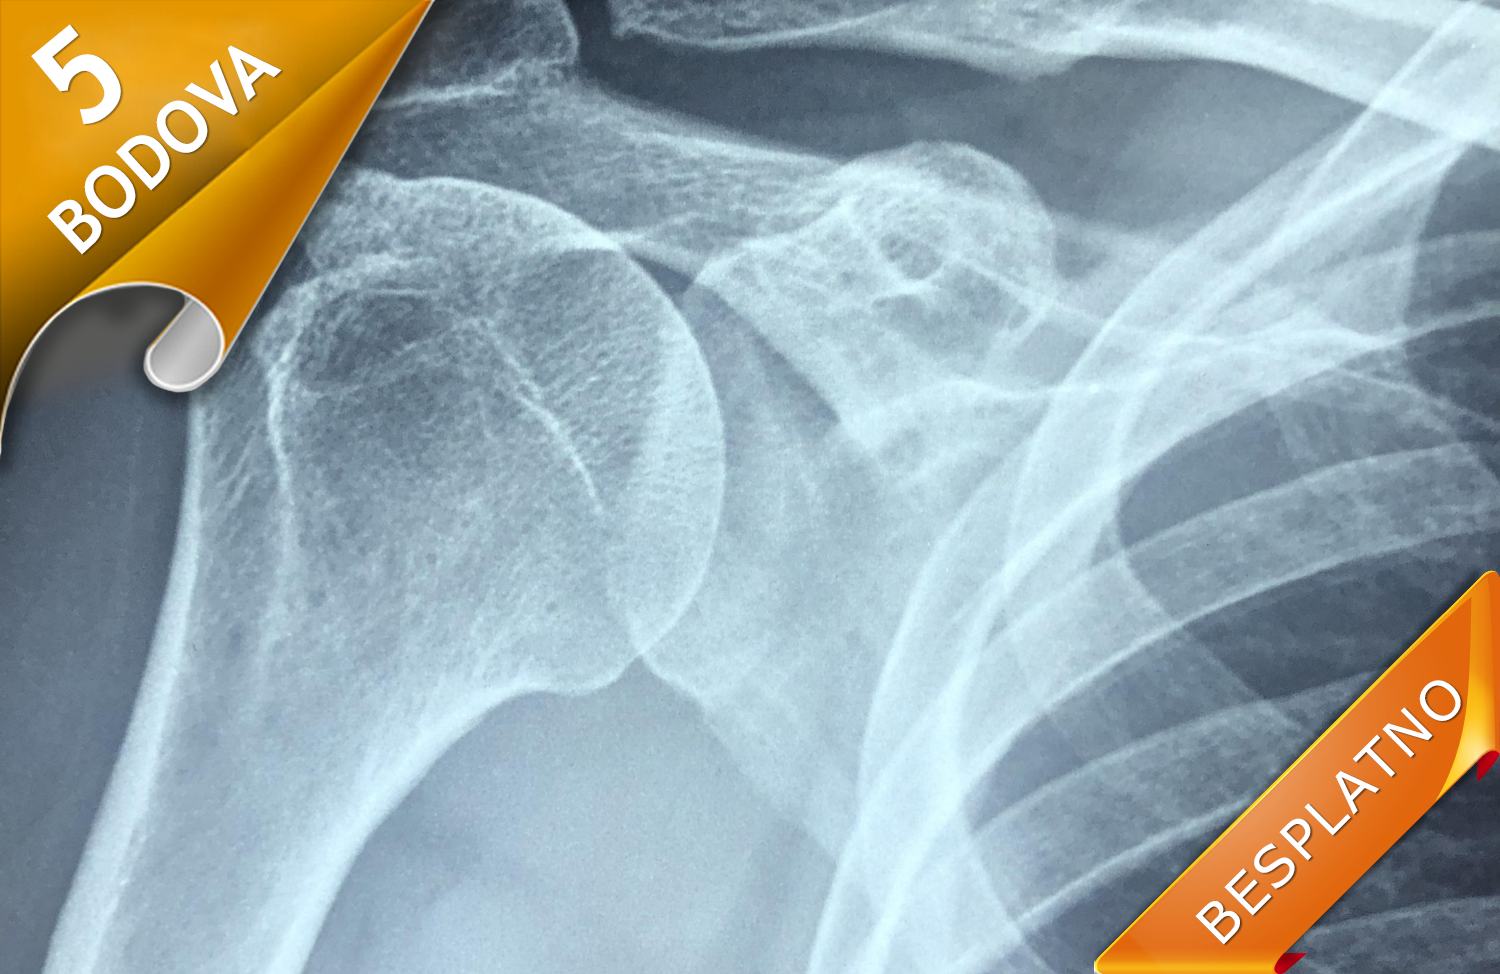

METABOLIČKE BOLESTI KOSTIJU KOD DECE